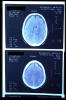

AVC amplio de territorio de A. cerebral media